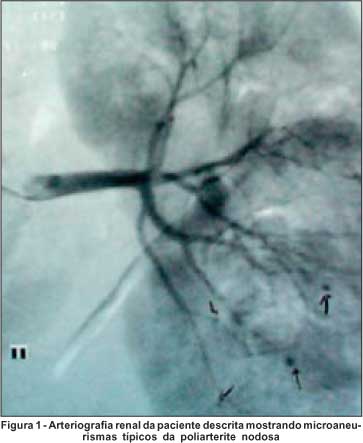

RFC, sexo feminino, 26 anos, tem diagnóstico de PAN a 6 meses antes do evento atual quando apresentou quadro de hipertensão arterial, mononeurite multiplex em membro superior D e inferior D além de vasculite retiniana com diminuição abrupta da acuidade visual do olho direito. Na época esteve internada no serviço de Reumatologia do HUEC tendo sido submetida à investigação que mostrou: pesquisa de fator antinuclear e sorologias para hepatite B, C, HIV negativas; complementos (C3 e C4), creatinina e hemograma normais. As provas de atividade inflamatória eram altas com VHS de 84 mm na primeira hora e proteína C reativa de 96 mg/l e o parcial de urina mostrava traços de proteína e ++ de cilindros hialinos por campo de grande aumento. Uma angiografia mesentérica e renal mostrou múltiplos microaneurismas na topografia de artérias segmentares intra-renais sendo, portanto, compatível com diagnóstico de PAN (Figura 1).